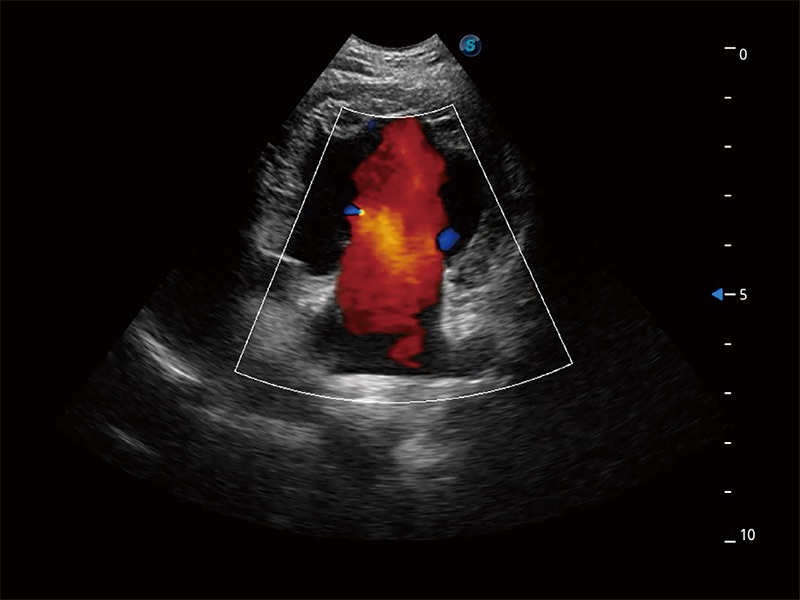

ProPet 80 配备了丰富的心脏探头群、先进的成像技术和专业的心脏测量工具,可帮助动物医生为不同体型和生理结构的动物提供心脏和心肌功能的全面评估。

能够增加心肌组织与血流之间的区别。对于心脏扫查困难的动物,可提供更好的心内膜边界的显示。

能够基于左心室壁追踪和辛普森法,自动计算射血分数,支持多个可移动点描迹,与手动测量相比,极大节省了动物医生的时间和精力。